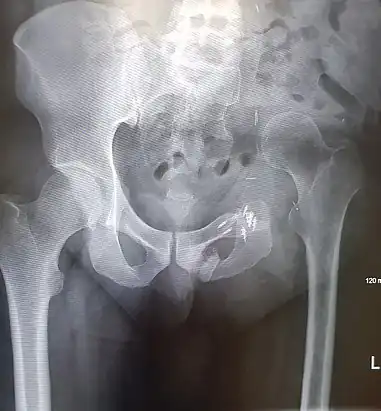

Prior to performing a hemipelvectomy, surgeons must possess detailed knowledge of the pelvic anatomy and its relation to the pelvic tumor.[1] Imaging studies such as conventional radiography, computed tomography, and magnetic resonance imaging help the surgeon visualize the anatomy and its relationship to the local pathology.[1] Surgical oncology techniques are utilized when resecting tumors of the pelvis.[1] Such techniques ensure that adequate resection margins are obtained at the time of surgery to minimize tumor recurrence.[1]

The Enneking and Dunham classification system was developed in 1978 to aid surgeons in characterizing pelvic resections.[1][3][4] This classification scheme breaks down pelvic resections into 3 subtypes: Type I, Type II, and Type III.[1][3][4] Type I resections involve removal of the ilium.[1][3][4] Type II resections involve removal of the peri-acetabular region.[1][3][4] Type III resections involve removal of the ischial and/or pubic region.[1][3]

Resection of pelvic bone typically requires subsequent reconstruction to ensure stability of the hip joint, particularly in internal hemipelvectomy.[1] Examples of pelvic reconstruction include the use of an allograft, autograft, or prosthesis to bridge the remaining ends of pelvic bone following resection.[1][4] Arthrodesis is a technique that can be used in internal hemipelvectomy to fix the proximal femur to a segment of pelvic bone for the purposes of stabilizing the lower extremity.[1][4]

Images